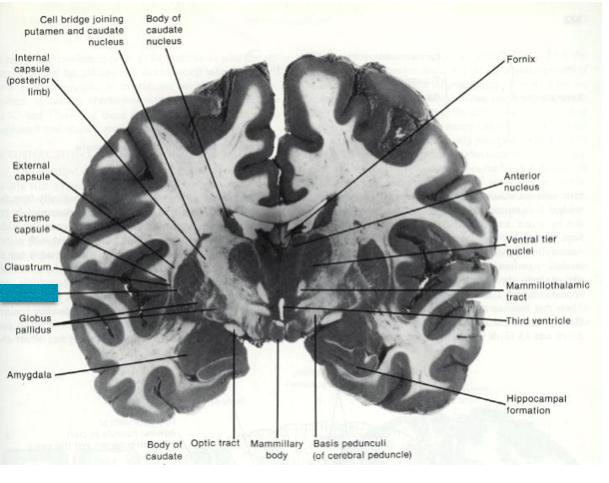

Fill in the blanks.

Fill in the blank.

Fill in the blank

Fill in the blanks